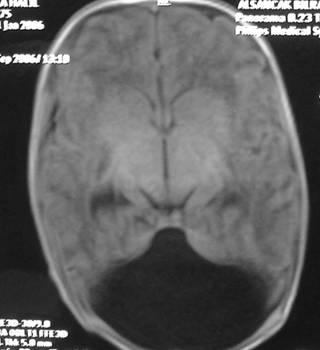

DWM arka çukur denen kafatası içinde beyincik, beyin sapı ve dördüncü karıncığın yer aldığı boşluğun doğumsal kusurudur. Beyinciğin vermis denen orta kısmı ya hiç gelişmemiştir ya da çok az bir kısmı gelişmiştir. Dördüncü karıncık genişleyip kistik bir hal almıştır (Resim 1). Bu kistik genişleme beyin omurilik sıvısının (BOS) dördüncü karıncığı terk ettiği deliklerin kapalı olmasına bağlanmaktadır. Bu hastaların %90’ında hidrosefali bulunmaktadır ve %75-80’inde doğumdan sonra ilk 3 ayda hidrosefali mevcuttur. DWM 25000-30000 canlı doğumda 1 görülmektedir.

Resim 1: (a ve b)Yatay MR görüntülerinde beyinciğin orta kısmının (vermis) gelişmemiş olduğu ve dördüncü karıncığın genişlemiş olduğu, (c) yan MR görüntüsünde kistik dördüncü karıncık izlenmektedir.